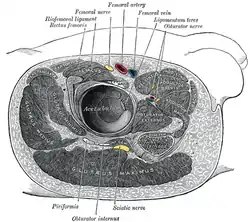

Position of gluteus minimus muscle (shown in red). Hip bone is shown in semi-transparent.

Position of gluteus minimus muscle (shown in red). Hip bone is shown in semi-transparent. Structures surrounding right hip-joint. (Gluteus minimus visible at center left.)